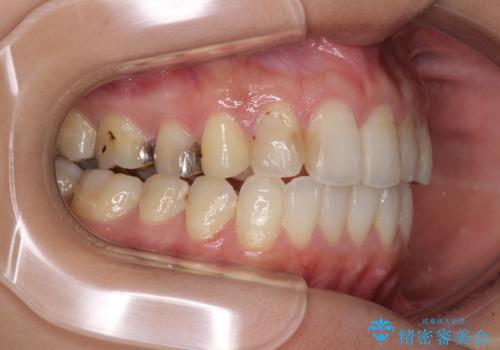

後戻りを治したい 骨格的なズレの大きい方のインビザライン矯正

- 中学生の時に矯正治療をしたものの、後戻りを気にして来院された患者様です。

骨格的に下顎が右側に変位しているため、左右の咬み合わせを理想的なものに改善することはできませんが、インビザラインにて歯列を整えることとしました。

骨格的なズレによる左右差は改善できませんでしたが、上下の正中を極力合わせるようにすることができました。